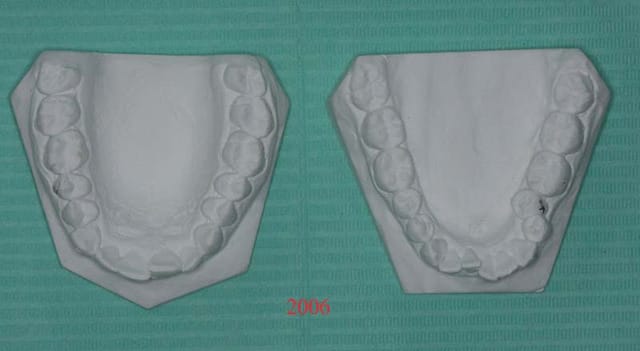

Modèles de départ

traité il y a 3 ans, avec extraction

et les photos d'arcades

la patiente est inquiète car malgré la contention Inf.

"ça revient comme avant"

2 s3z7di - Eugenol

3 aezt8f - Eugenol